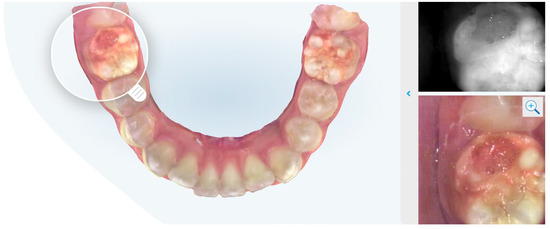

Figure 3.

Example of intraoral scan with evidence of MIH.

In the population taken into consideration in this study, children between 6 and 12 years old who underwent the intraoral scan and who participated in the completing the questionnaire at the Department of Pediatric Dentistry of the University of L’Aquila, we found that the Italian version of the “questionnaire on the effectiveness and satisfaction of the intraoral scanner in the growing patient”, developed by a group of Italian native speakers of different disciplines, has demonstrated good internal consistency and moderate retest reliability, satisfying its validity. The relatively limited size of the study did not allow us to find statistically significant differences based on gender. In agreement with the results of the questionnaire, we can state that the scanning of the arches, through the use of intraoral scanner, has the ability to positively interfere in generating awareness in the parent about the child’s health, can interact in the trinomial dentist-child–parent communication and can be considered useful for detection of the footprint. For this last point, the results of the questionnaire confirm what already exists is present in the literature. The Italian version of the questionnaire proposed to children patients and their parents enjoys a satisfactory internal coherence index. Indeed, Cronbach’s alpha had a value of 0.728. Test–retest reliability was moderate for four questions (for Q4, Q9, Parent’s Q11 and Child’s Q1) with a score ICC between 0.5 and 0.75. The remaining questions were considered statistically insignificant, having a score less than 0.5. Regarding the reliability of the dichotomous variables, the Cohen’s kappa index stands at 81.75%; for this reason, it is considered highly reliable. Previous studies have shown how visualization and understanding the treatment helps the patient follow through the indications provided by the clinician. This mechanism is very similar to the behavioral technique Tell–Show–Do already present in the literature. From the results, in fact, we note that the visualization of the reconstruction of the model in 3D generates in the patient, rather than in the parent, a higher level of understanding (Figure 2 and Figure 3).

It has also been shown in the past that children show a greater acceptance of medical care when using digital technologies [21]. Furthermore, patients whose dental treatment included intraoral scanning reported greater comfort and less chair time compared to conventional impression techniques [22]. Especially when dealing with younger or more anxious patients, a skeptical attitude towards treatment can lead to lower treatment acceptance due to a lack of understanding of the need for treatment [23]. Special conditions such as MIH require intensive, long-term treatment. If the affected teeth are visualized to the patient and their carers during previous examinations, this can lead to a better acceptance of the planned treatment and therefore better preservation of the teeth.